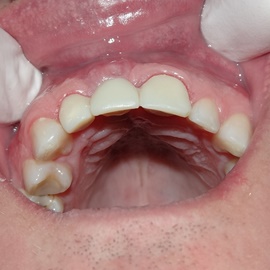

Bezzębie całkowite górne. Początkowo wykonane na mieście mosty całoceramiczne wydawały sie sukcesem, ale po roku pojawiły sie obrzęki i krwawienie z dziąseł. Pacjentka zgłosiła się do leczenia. Usunięto wszystkie zęby w szczęce. Sterowana regeneracja tkanek kości wyrostka, modelowanie kształtu i objętości tkanek miękkich, mosty porcelanowe przykręcane do implantów. Zadowalający wynik anatomiczny i estetyczny.